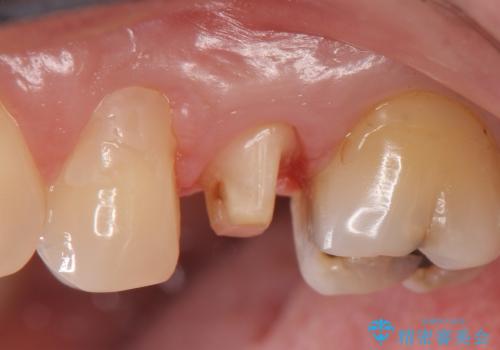

- 左上5番目の歯がしみるといらっしゃった方の症例です。

頬側の樹脂及び銀歯を除去後、オールセラミッククラウンにて補綴を行いました。